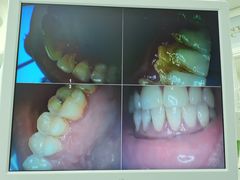

• 牙博士口腔品牌连锁(杨浦店)

• -牙博士口腔品牌连锁(杨浦店)

猜猜我是谁 | 21-12-12